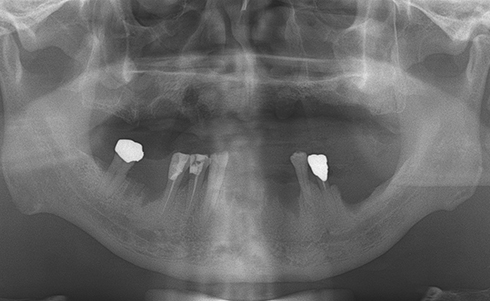

Fully edentulous clinical cases